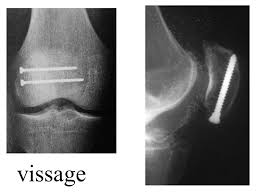

Ci après quelques illustrations de traitement chirurgical :

Vissage de rotule